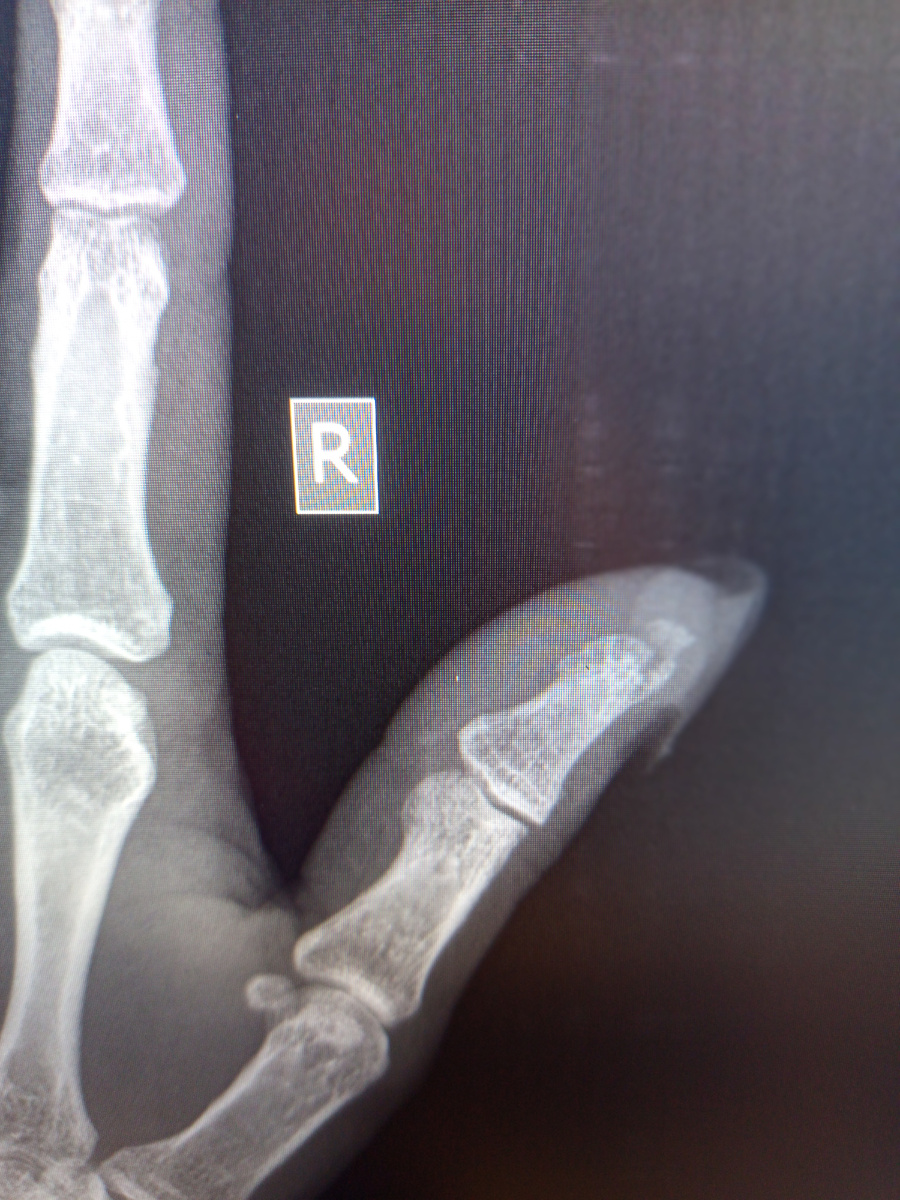

Парнишка зашел, 20 лет , балка упала на кисть.

–Где на тебя свалилась балка? Дома?

–Если бы , да я подработать на лето решил, лучше б отдыхать поехал!

–Погоди ты! Может , просто ушиб ! Снимки надо сделать сначала.

–Да перелом это , болит же!

–Ушибы тоже болят , давай , ладонью вниз руку делай.

-5

-6

Третий ,четвёртый пальцы.

–Ну , скажите , я прав?

Прав-прав! Иди к врачу.